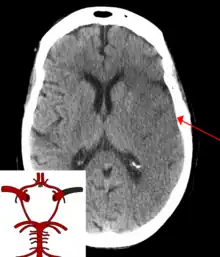

| CT scan of the brain showing a prior right-sided ischemic stroke from blockage of an artery. Changes on a CT may not be visible early on.[1] | |

The main risk factor for stroke is high blood pressure.[6] Other risk factors include tobacco smoking, obesity, high blood cholesterol, diabetes mellitus, a previous TIA, end-stage kidney disease, and atrial fibrillation.[2][6][7] An ischemic stroke is typically caused by blockage of a blood vessel, though there are also less common causes.[12][13][14] A hemorrhagic stroke is caused by either bleeding directly into the brain or into the space between the brain's membranes.[12][15] Bleeding may occur due to a ruptured brain aneurysm.[12] Diagnosis is typically based on a physical exam and supported by medical imaging such as a CT scan or MRI scan.[8] A CT scan can rule out bleeding, but may not necessarily rule out ischemia, which early on typically does not show up on a CT scan.[9] Other tests such as an electrocardiogram (ECG) and blood tests are done to determine risk factors and rule out other possible causes.[8] Low blood sugar may cause similar symptoms.[8]